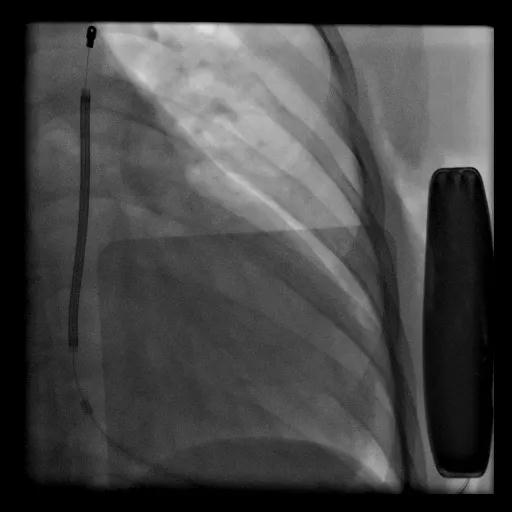

2021年1月6日,上海交通大学医学院附属瑞金医院心脏内科成功为一位20岁女性扩张性心肌病患者植入该院首例全皮下植入式心律转复除颤器(S-ICD)。

瑞金医院心脏内科S-ICD植入团队